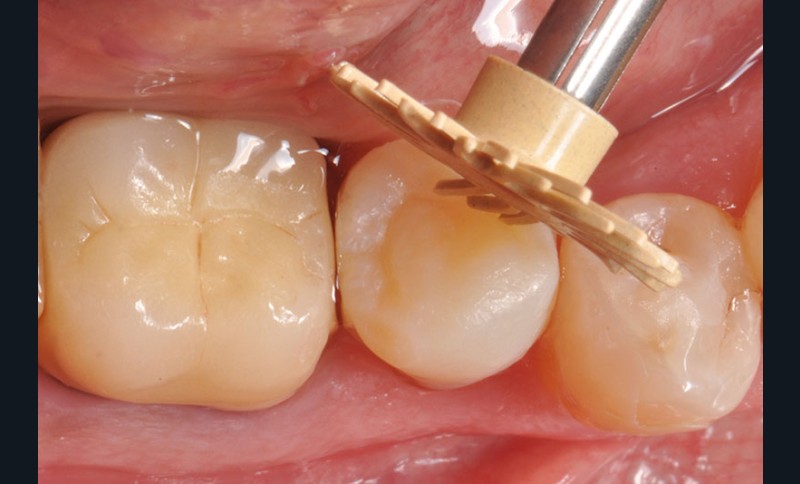

3, 4, 5. La restauration est déposée, les tissus carieux éliminés et la cavité d’accès aménagée avant la réalisation du traitement endodontique. La radiographie postopératoire permet de visualiser l’obturation du canal latéral en regard de la LIPOE.